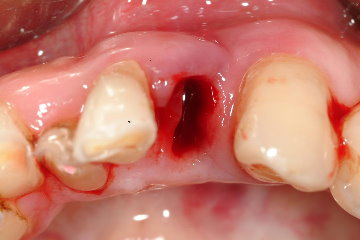

圖二 |

因此本次治療的計畫為

一、立即拔牙

二、立即植牙(下顎前牙之齒槽骨與人工植牙形態相近,並且患者不需再次手術)

三、骨粉及再生膜修補骨質破損處

四、早期受力(由於下顎骨為硬骨質居多,因此2-4週內即可完成假牙重建)